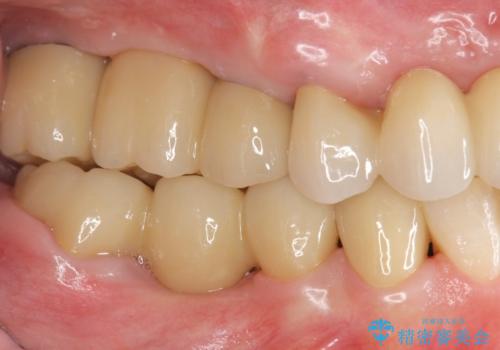

多発した虫歯による咬合崩壊 インプラントを用いた全顎治療

- 「これまで歯の治療をおざなりにしてしまい本当に後悔している。 時間と費用がかかってもいいので、しっかりと安心してかめるような状態にしてほしい。」、と全体的な治療を希望され来院されました。

歯の破折・再発した大きな虫歯・根尖病変・歯の欠損、これらの問題を根管治療・歯周外科・インプラント治療・セラミック補綴を行うことで一つづつ解決し安定した咬合状となるよう治療を進めます。